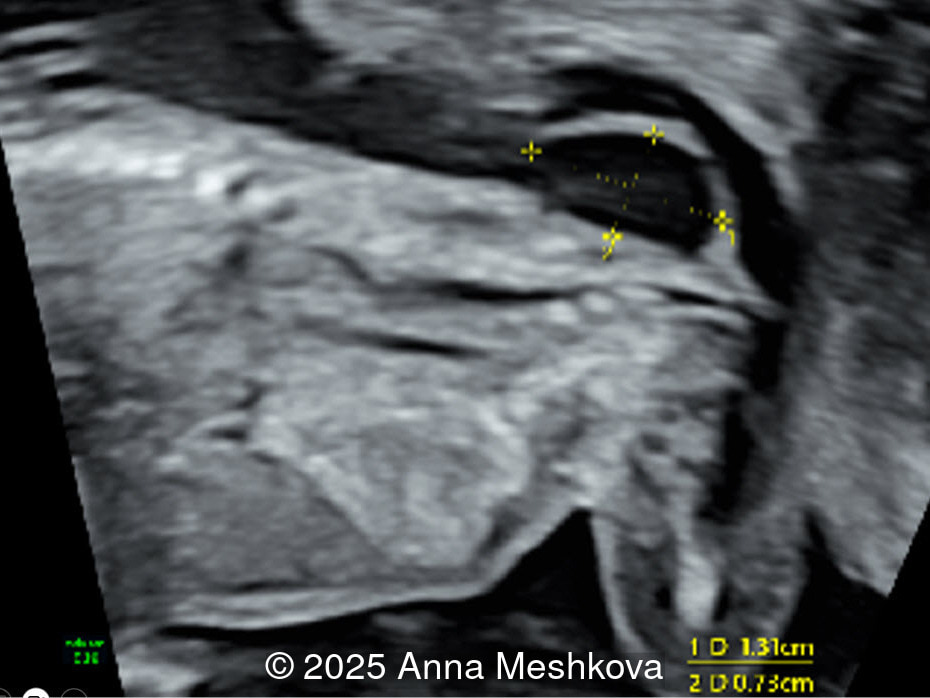

• Image 2:  Transverse section of the brain at the level of the aqueduct of Sylvius. Midbrain is seen juxtaposed to the occiput, known as "crash" sign.

Image 2 3D reconstruction of the spinal defect in the lumbosacral region at 13 weeks gestation